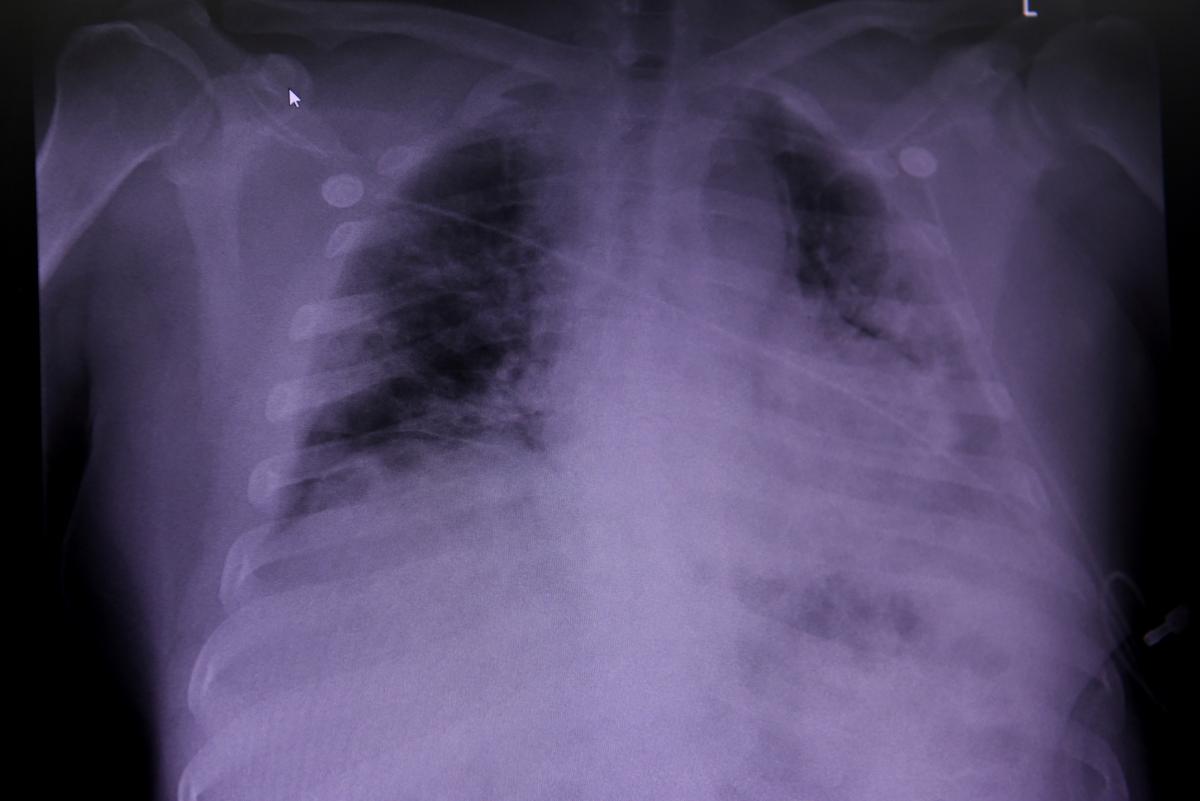

Пневмония при коронавирусе: пульмонолог назвал особенности

Кандидат медицинских наук, хирург органов грудной клетки и пульмонолог Евгений Симонец сообщил, что врач с помощью фонендоскопа может не распознать пневмонию при коронавирусе COVID-19. При бактериальных... glavred.info »

КТ и рентген при коронавирусе, когда нужно делать и вообще стоит ли: объяснение львовской врача

Врач Наталья Шоробура говорит, что при обнаружении вирусной пневмонии на КТ, лечение пациента от того, как правило, не меняется. ru.tsn.ua »

Что лучше делать для диагностики коронавируса – КТ или рентген: врач-инфекционист объяснил детали

Евгений Дубровский: "Писать, что на КТ при COVID-19 двусторонняя пневмония – некорректно. Описывать матовые стекла как проявления пневмонии — ошибка". ru.tsn.ua »